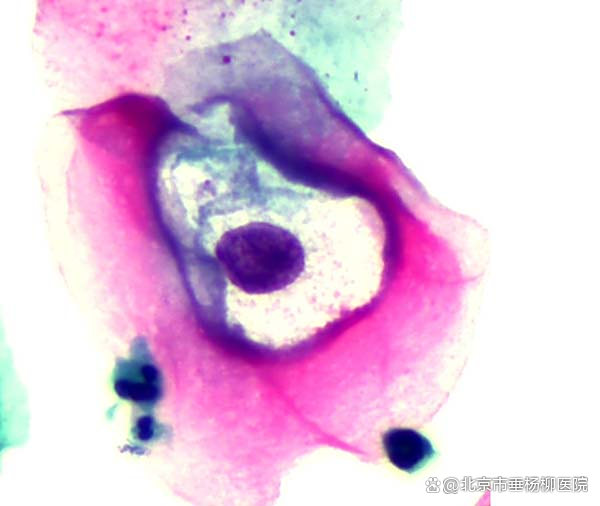

HPV病毒感染

HPV目前分为高危,低危和疑似高危三种类型,持续性的高危病毒感染会大大增加女性宫颈癌的发生率。